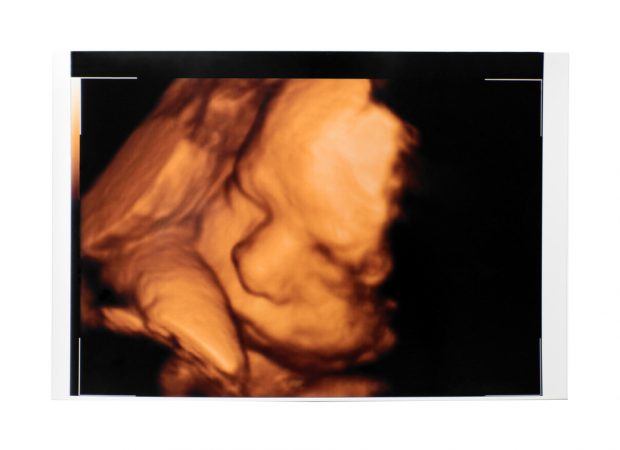

Über Geschmack lässt sich bekanntlich nicht streiten, der ist einfach gegeben. Kinder mögen zum Beispiel selten grünes Gemüse, das wissen alle eifrigen Eltern, die ihren Nachwuchs gern gesund ernähren würden – es aber nicht ganz schaffen. Auch viele Große kommen nicht gut mit Spinat, Grünkohl und Co. zurecht, obwohl sich im Laufe der Jahre der Geschmack doch deutlich in Richtung »Grünzeug« verschiebt. Forscher wollten nun wissen, ob Babys im Mutterleib auf bestimmte Speisen spezifisch reagieren und wie diese Reaktionen aussehen. Symbolfoto Baby im Mutterleib Karotten zaubern den Babys ein Lächeln ins Gesicht Wissenschaftler an der Durham University rüsteten sich mit einer Ultraschallkamera und verschiedenen Gemüsekapseln. Als Probanden luden sie Schwangere im fortgeschrittenen Stadium zu sich ein, um die Gesichter der Babys studieren zu können. Wie würden die Kleinen auf Grünkohl und Karotten reagieren? Karotten sind bekanntlich eine beliebte Beigabe zum Babybrei, ihr süßlicher Geschmack ist bei den Jüngsten beliebt. Das zeigte sich auch bei dieser Studie: Breitete sich der Geschmack nach Karotten im Fruchtwasser aus, zauberte das den Babys ein Lächeln aufs Gesicht! Unverkennbar gingen die Mundwinkel nach oben und Zufriedenheit stellte sich. Versuchen Sie mal, einem Durchschnittsbaby statt Karotten Grünkohl zu geben, das könnte in einer Grünkohldusche enden! Auch im Mutterleib ist das bereits erkennbar. Auf den Ultraschallbildern zeigten sich nach der Einnahme von grünem Gemüse unzufriedene, teils sogar weinende Gesichter. Aßen die Mütter gar nichts, blieben die Babymienen meistens neutral. Woran mag es liegen? Was ist der Grund für diese Empfindlichkeiten? Vielleicht liegt die instinktive Abneigung gegen Kohlgeschmack daran, dass dieses und ähnlich geartete Gemüse Blähungen erzeugen. Babys und Kleinkinder sind an diesem Punkt sehr empfindlich, das weiß jeder, der schon einmal den Bauch eines sich windenden Säuglings massieren musste. Die »bittere Pille« hat also oftmals noch andere Nebenwirkungen als nur ihren Geschmack. Die Kleinen wissen nichts davon, aber vielleicht ahnen sie es. Quelle: badische-zeitung.de Teile den Artikel oder unterstütze uns mit einer Spende. Facebook Facebook Twitter Twitter WhatsApp WhatsApp Email E-Mail Newsletter